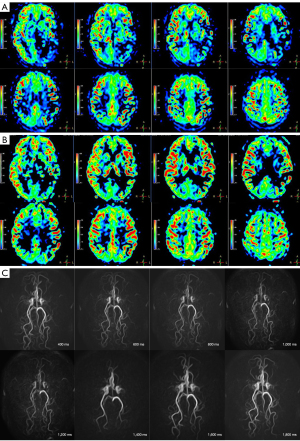

The patient’s MDT initially considered intervention or revascularization surgery as the optimal treatment to reduce the frequency of recurrent TIAs and the risk of infarction. However, repeated ASL indicated that the patient’s cerebral hemodynamic impairments and collateral blood flow were not consistent with those of typical MMD. The patient’s ASL data were acquired with three-dimensional pseudo-continuous ASL (3D-pCASL) using the following parameters: labeling duration =1.5 s, postlabeling delay (PLD) =1.5/2.5 s, repetition time (TR) =3.7/4.7 s, echo time (TE) =11 ms, field of view (FOV) =240 mm × 240 mm × 85 mm, matrix =64×64, thickness =6 mm, and duration time =5 minutes and 21 seconds/6 minutes and 47 seconds. In 2013, the patient’s 3D-pCASL images showed serpiginous high signal intensity in the bilateral cerebral cortex and sulcus at a PLD of 1.5 s (Figure 4A), and, less prominently, in the bilateral temporal and parietal cortex at a PLD of 2.5 s (Figure 4B). From 2013 to 2020, 3D-pCASL at PLD of 1.5 and 2.5 s continuously demonstrated bright hyperintensity in the cerebral symmetric cortical surface. In 2021, the 3D-pCASL-based dynamic MRA referred to as “four-dimensional magnetic resonance angiography (4D-MRA)” and 3D-pCASL were performed on a new 3.0-Tesla MRI scanner (Ingenia CX, Philips) using 32-channel head coils. The latest ASL images showed hyperintense signal bands in the bilateral hemisphere at a PLD of 1.5 s (Figure 5A) and, much more prominently, at a PLD of 2.5 s (Figure 5B). Meanwhile, 4D-MRA data were acquired with the time-resolved angiography non-contrast-enhanced (TRANCE) technique using the following parameters: TR =9.3 s, TE =4.8 s, FOV =210 mm × 210 mm × 80 mm, spatial resolution =1.2 mm × 1.2 mm × 1.3 mm, matrix =172×130, thickness =1.3 mm, label delay =200 ms, label gap =20 mm, phase interval =200 ms, phases =10, and duration time =2,200 ms. Symmetrical emergence of bilateral PCAs was observed, and intracranial collaterals originating from the bilateral PCAs were clearly shown on the dynamic 4D-MRA (Figure 5C).

Between 2013 and 2020, the intensity of ATA on the patient’s ASL images at a PLD of 1.5 s was much more significant than that of 2.5 s, which suggested that the antegrade blood flow was comparatively faster. The latest ASL in 2021 showed that the intensity of ATA at a PLD of 2.5 s was much more intensive than before, which may suggest that the arterial transit time of the collaterals is longer than the anterograde blood flow. ATA is dependent on the arterial transit time and is influenced particularly by the labeling time and PLD. The decreased and slow blood flow might induce an ATA; therefore, cortical flow in moyamoya patients may resemble this hemodynamic status. The strength of the ATA alters according to the PLD value because the delayed blood flow due to stenosis or occlusion still remains in the cortical surface (24,27). Regarding this patient, ASL acquisitions with both shorter and longer PLD dramatically demonstrated conspicuous ATA in the bilateral hemispheric cortex, and this status has lasted almost 10 years to date. ATA has been reported to correlate with the development of collateral circulation and to reflect the presence of leptomeningeal collaterals on DSA (28). The balance of hemodynamics and compensated perfusion of this patient relies on slow flow from the collaterals of the posterior circulation, which prolongs the mean transit times of arterial blood flow and creates ATA on 3D-pCASL images. 4D MRA is a 3D-pCASL-based dynamic MRA with long labeling duration, which can ensure visualization of the complete arterial trees from proximal to distal vessels with adequate image quality (29). The patient’s latest 4D-MRA clearly shows the presence of collaterals mainly from the bilateral PCAs. Consequently, preservation and improvement of collateral blood flow can provide protection against future strokes and reduce the frequency of ischemic symptoms while effecting a concurrent reduction in collaterals.